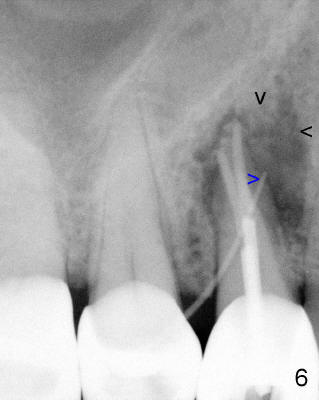

A 68-year-old male patient presented to office in March 2011 with chief complaint "upper right tooth is not comfortable". Clinical exam shows missing teeth: #13,14,30, and 31, replaced by removable partial dentures. The tooth #5 has mild mobility and percussion. Pocket depth is within normal limit. X-ray shows no significant finding (Fig.1,2). Three months later, he returned with chief complaint "The tooth has swelling". It appears that there is exostosis on buccal aspect of upper teeth. There is no erythema or tenderness on buccal mucosa around the tooth #5). But X-ray shows periradicular radiolucency (arrowheads in Fig.3,4). Cone Beam CT was recommended to confirm diagnosis of root fracture. Approximately one month later, abscess developed with fistula formation. Symptoms were controlled by taking Amoxicillin. On August 2, 2011, the patient returned for prophylaxis. The fistula was present (arrowhead in Fig.5). Gutta percha #30 was inserted into the fistula. PA was taken. The point of the gutta percha (blue arrowhead in Fig.6) points to enlarged periradicular radiolucency (black arrowheads). Deep pockets were in distobuccal and lingual. Decision was made to extract the tooth. Fig.7 shows the socket immediately extraction. The buccal plate is perforated. The septum (*) is not intact. Cracking sounds were heard during extraction. In fact the lingual root is obliquely fractured with exposed post (Fig.8: *). There is another cracking line from the buccal root to the lingual one (arrowhead). In brief, the earliest sign of root fracture is nonspecific. It should alert us to its suspicion.